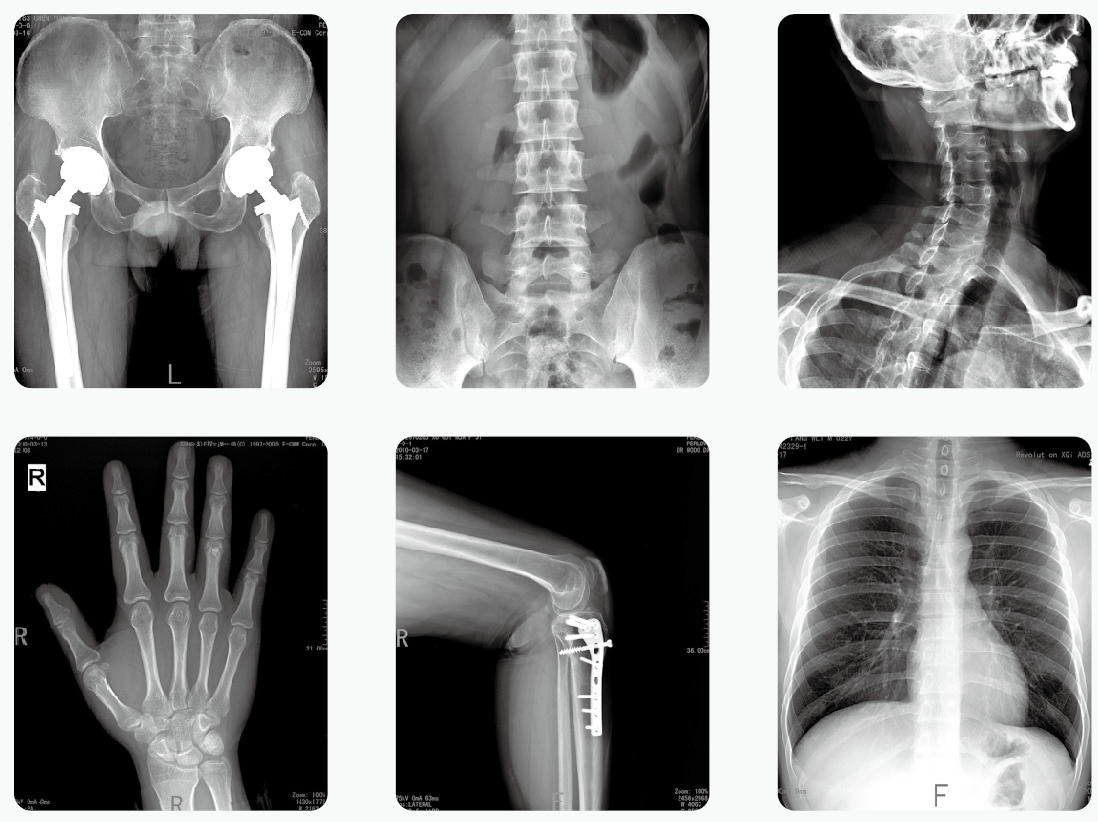

通過醫(yī)用X光機檢查,臨床醫(yī)生可以獲取病人很多重要的,甚至性命攸關(guān)的醫(yī)療信息,比如肺炎、骨折、腸梗阻等。這些普通X光檢查,對平常人而言就像是拍數(shù)碼照相,咔~可以了。但是對孕婦而言,有時的確是一個艱難的決策。那么,醫(yī)用X光機檢查,孕婦到底能不能做?

其實,絕大部分醫(yī)用X光機檢查的部位都是四肢、頭、牙齒或者胸部,孕婦的生殖腺并沒有直接暴露在X光下。因此,在這些情況下,只要合理曝光及防護,對胎兒是沒有危害和影響的。

但是,如果孕婦需要做腹部、盆腔、腰椎等醫(yī)用X光機檢查,此時胎兒是直接暴露在X光下的,這種情況就需要與醫(yī)生探討X光檢查的利弊后再做決定。